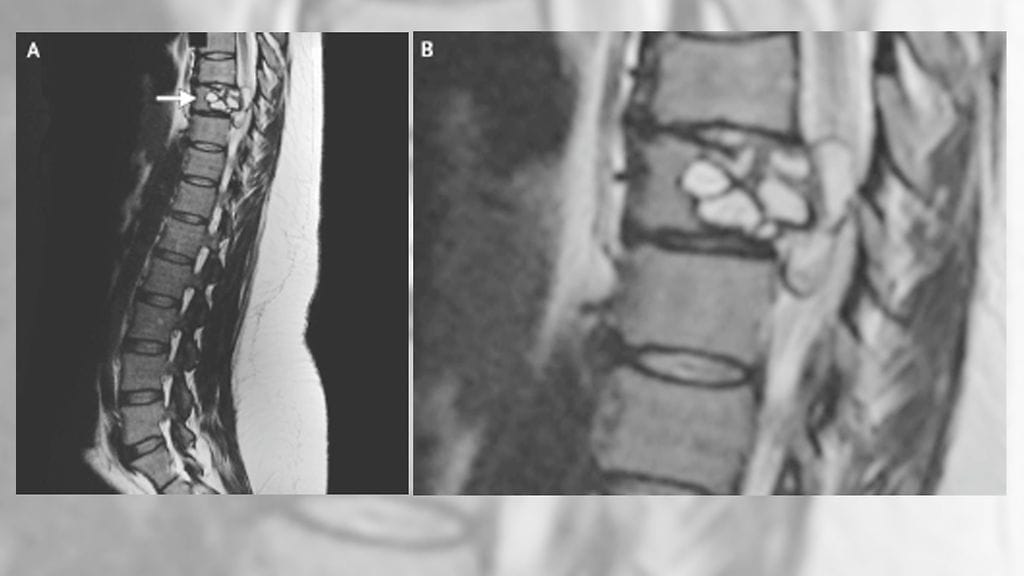

The New England Journal of Medicine -verkkojulkaisussa nimittäin todetaan, että lääkärit löysivät naisen selkärangasta Echinococcus granulosus -lajin heisimadon. Keskelle selkärankaa pesiytynyt loinen oli poistettava leikkauksella.